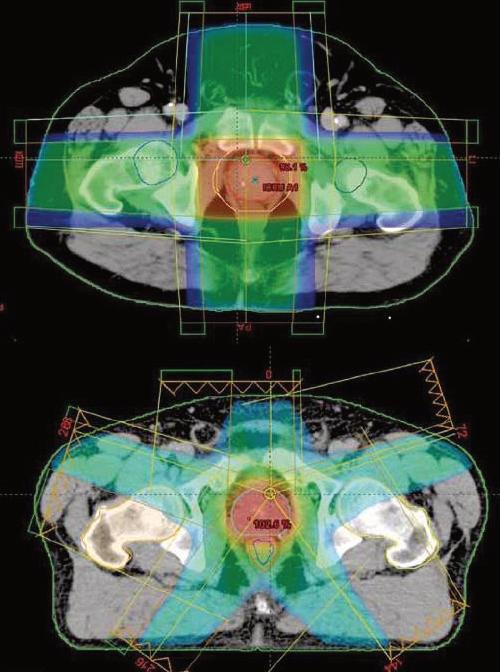

Lastécnicasmásnuevasderadioterapiade rayosexternosenfocanlaradiaciónconmás precisióneneltumor.Estopermitequelosmé‐dicosadministrendosismásaltasderadiación altumoralavezquesereducelaexposiciónde radiaciónalostejidossanosadyacentes.

Estetipoderadioterapiautilizacomputadoras especialesparadeterminarconprecisiónla

ubicacióndesupróstata.Entonceslosrayos delaradiaciónsonconfiguradosydirigidosa lapróstatadesdevariasdirecciones,loque hacemenosprobablesquehayadañosalos órganosytejidosnormalescircundantes.

RADIOTERAPIADEINTENSIDADMODULADA

Laradioterapiadeintensidadmodulada (IMRT),unaformaavanzadadeterapia3DCRT,eseltipoderadioterapiaconrayoexterno máscomúnparaelcáncerdepróstata.Esta técnicaempleaunamáquinacontroladapor unacomputadoraquesemuevealrededordel pacienteamedidaqueemitelaradiación. Ademásdeconfigurarlosrayosydirigirlosala próstatadesdevariosángulos,laintensidad (fuerza)delosrayospuedeserajustadapara limitarlasdosisderadiaciónquelleganalos tejidosnormalesadyacentes.Administrarla radiacióninclusodeformamásprecisa,loque conduceamenosefectossecundarios.Apro‐ximadamente30-40%

Ambastécnicassecuentanenel centrooncológicodecolimaUnidaddeRadioterapia,porloque seencuentraalapartecnológica decentroscomoGuadalajara, MonterreyyCDMX.

Superior:dosimetríadeirradiaciónprostática conplanificaciónconvencional3D.

Inferior:planificaciónIMRT.Eláreadedosis terapéutica(árearoja)seadaptamuchomejor alvolumenblancoconIMRT.